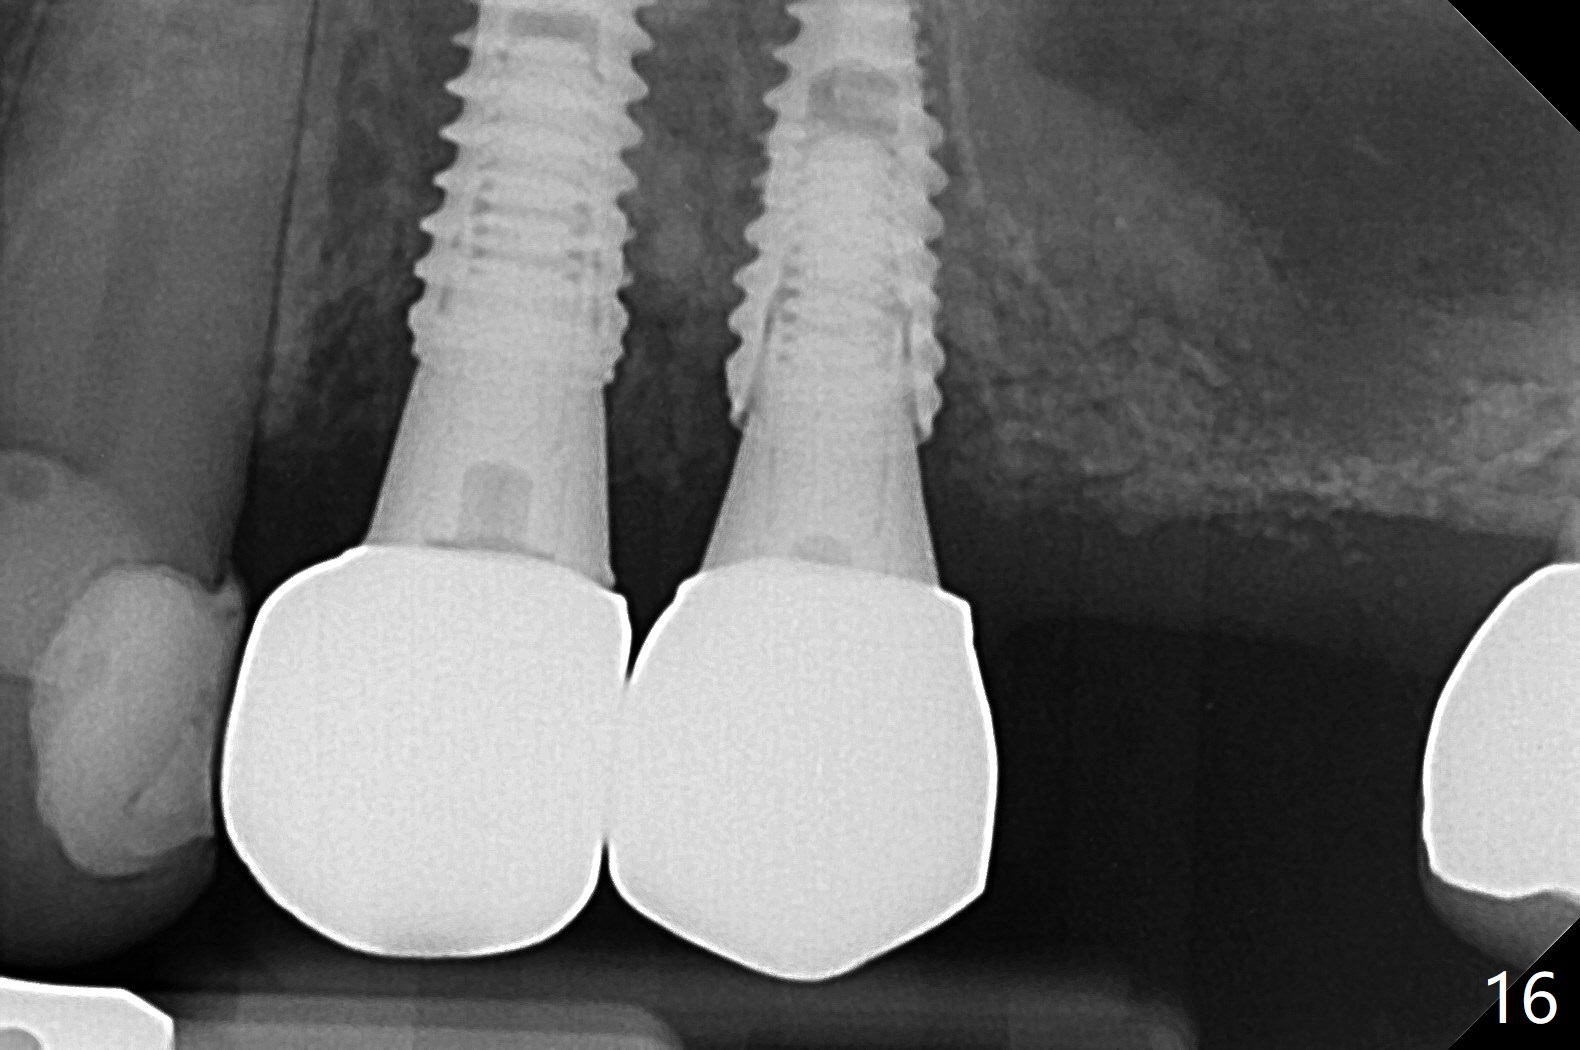

Osteotomy at #3 is performed last (Fig.1,2); as planned, a 4 mm cortical tap is used with guide for sinus lift. Unfortunately the sinus membrane is perforated. Implant placement is aborted. Instead Osteogen plug is inserted into the osteotomy, which is fixed in place by acrylic extending from the provisional at #4. Osteotomy for #3 implant will be attempted with control of the depth in 4 months. The patient has allergy to Amoxicillin (rash). When switching to Clindamycin, she develops diarrhea and loses 10 pounds. There is no abnormality at the site of #3 or 4 nearly 3 months postop (Fig.3). The next surgery will be most likely conducted without antibiotic 4 months postop. Try to draw blood for PRF. Take PA for #12 and 13 for possible impression. Remove the 3 temporary crowns, seat the guide across the arch and use no-stop fixture mounts at #4, and possibly 12 and 13. Follow the original drill sequence (check perforation after each drill, Fig.11) and use DIONavi sinus approach kit. Also load an appropriate stop for the round bur for sinus lift before hand. Mixture allograft with Metronidazole and PRF. In fact everything goes on as smoothly as planned. Osteotomy at #3 is underprep (3.5 mm in diameter drill instead of 4.0). The sinus floor appears to remain to be absent; 3.2 mm round bur is used for lift, alternating with water pumping. Following insertion of 3 pieces of PRF membranes and Vanilla Graft (Fig.4 *), a 4x10 mm dummy implant is placed. After additional bone graft (Fig.5 *), a final 4.5x7.3 mm implant is placed ~10 Ncm. The implant is placed deeper ~ 1 mm, followed by a 5.5x3 mm healing abutment (Fig.6). The implants at #12 and 13 seem to have osteointegrated (Fig.7). Impression is taken for #4, 12 and 13 with limited vertical space (Fig.8,9). An implant at #14 is being considered. There is faint bone graft around the apex of the implant 4 months postop (Fig.10). The implant sustains 25-30 Ncm torque when a 5.2x4(3) mm cemented abutment is placed. A permanent crown is cemented nearly 5 months postop (Fig.11). For the best cosmetic and masticating results, the occlusal surface should have certain degree of morphology, such as the buccal cusps (Fig.12 white curved lines). The abutment at #3 is placed and torqued to 30 Ncm before re-cementation of the repaired crown (increased occlusal surface contact). In fact the abutment at #4 is incompletely seated with a gap (Fig.13 <). The composite at #5 is dislodged while #3 crown is being repaired (*). The abutment at #4 is loose >1 year post cementation. The abutment remains incompletely seated (gap and longer apical space (double arrows)) when the abutment/crown complex rotates lingual mesiobuccal (Fig.14 curved arrow). Further proximal reduction and lingual rotation distobuccal leads to complete seating (Fig.15). It appears that incomplete seating at #13 is associated with hex mismatch (Fig.16, large apical space), which will be fixed next visit. One week later, the crown and abutment of #4 are seated together after crown repair (Fig.17). Since the abutment margin is subgingival, the crown is cemented, removed with abutment for residual cement removal and reseated with the abutment with torque at 30 Ncm. After this, the crown and abutment of #13 is reseated after mesiobuccal surface is trimmed (Fig.18), followed by pick up impression. A few days later, the crown/abutment are inserted together smoothly, the former cemented and the complex unscrewed for residual cement removal and last torqued at 30 Ncm without any X-ray confirmation.